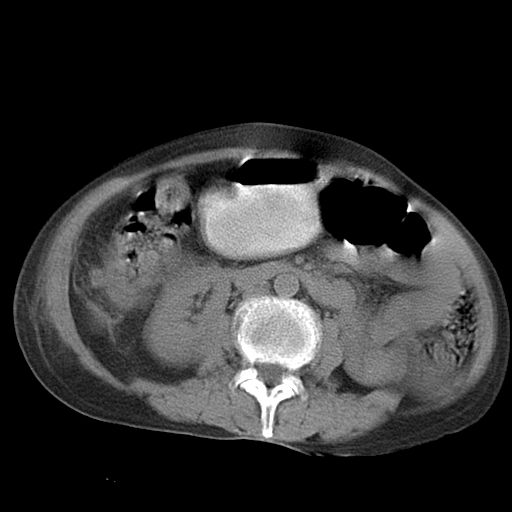

以下是引用dyqct在2006-12-7 21:08:00的发言:[br]考虑:1、肝内外胆管多发性结石伴肝左叶外侧段肝萎缩;[br] 2、右膈下多发脓肿;[br] 3、右侧少量胸腔积液、斜裂积液;[br] 4、左肾囊肿。

以下是引用jiazh在2006-12-7 20:37:00的发言:[br]肝脏周围半狐形低密度影,肝脏表面受压推移,考虑膈下脓肿可能性大;2、右侧胸腔积液

以下是引用拾荒者在2006-12-7 21:44:00的发言:[br]肝内外胆管多发结石,右膈下多发脓肿,右胸膜腔及叶间裂积液,左肾囊肿。[br] [br]